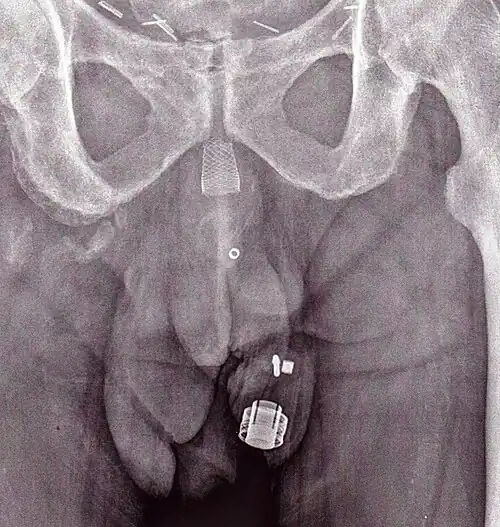

-

CT scan (coronal reconstruction) showing an AMS 800 in a woman -